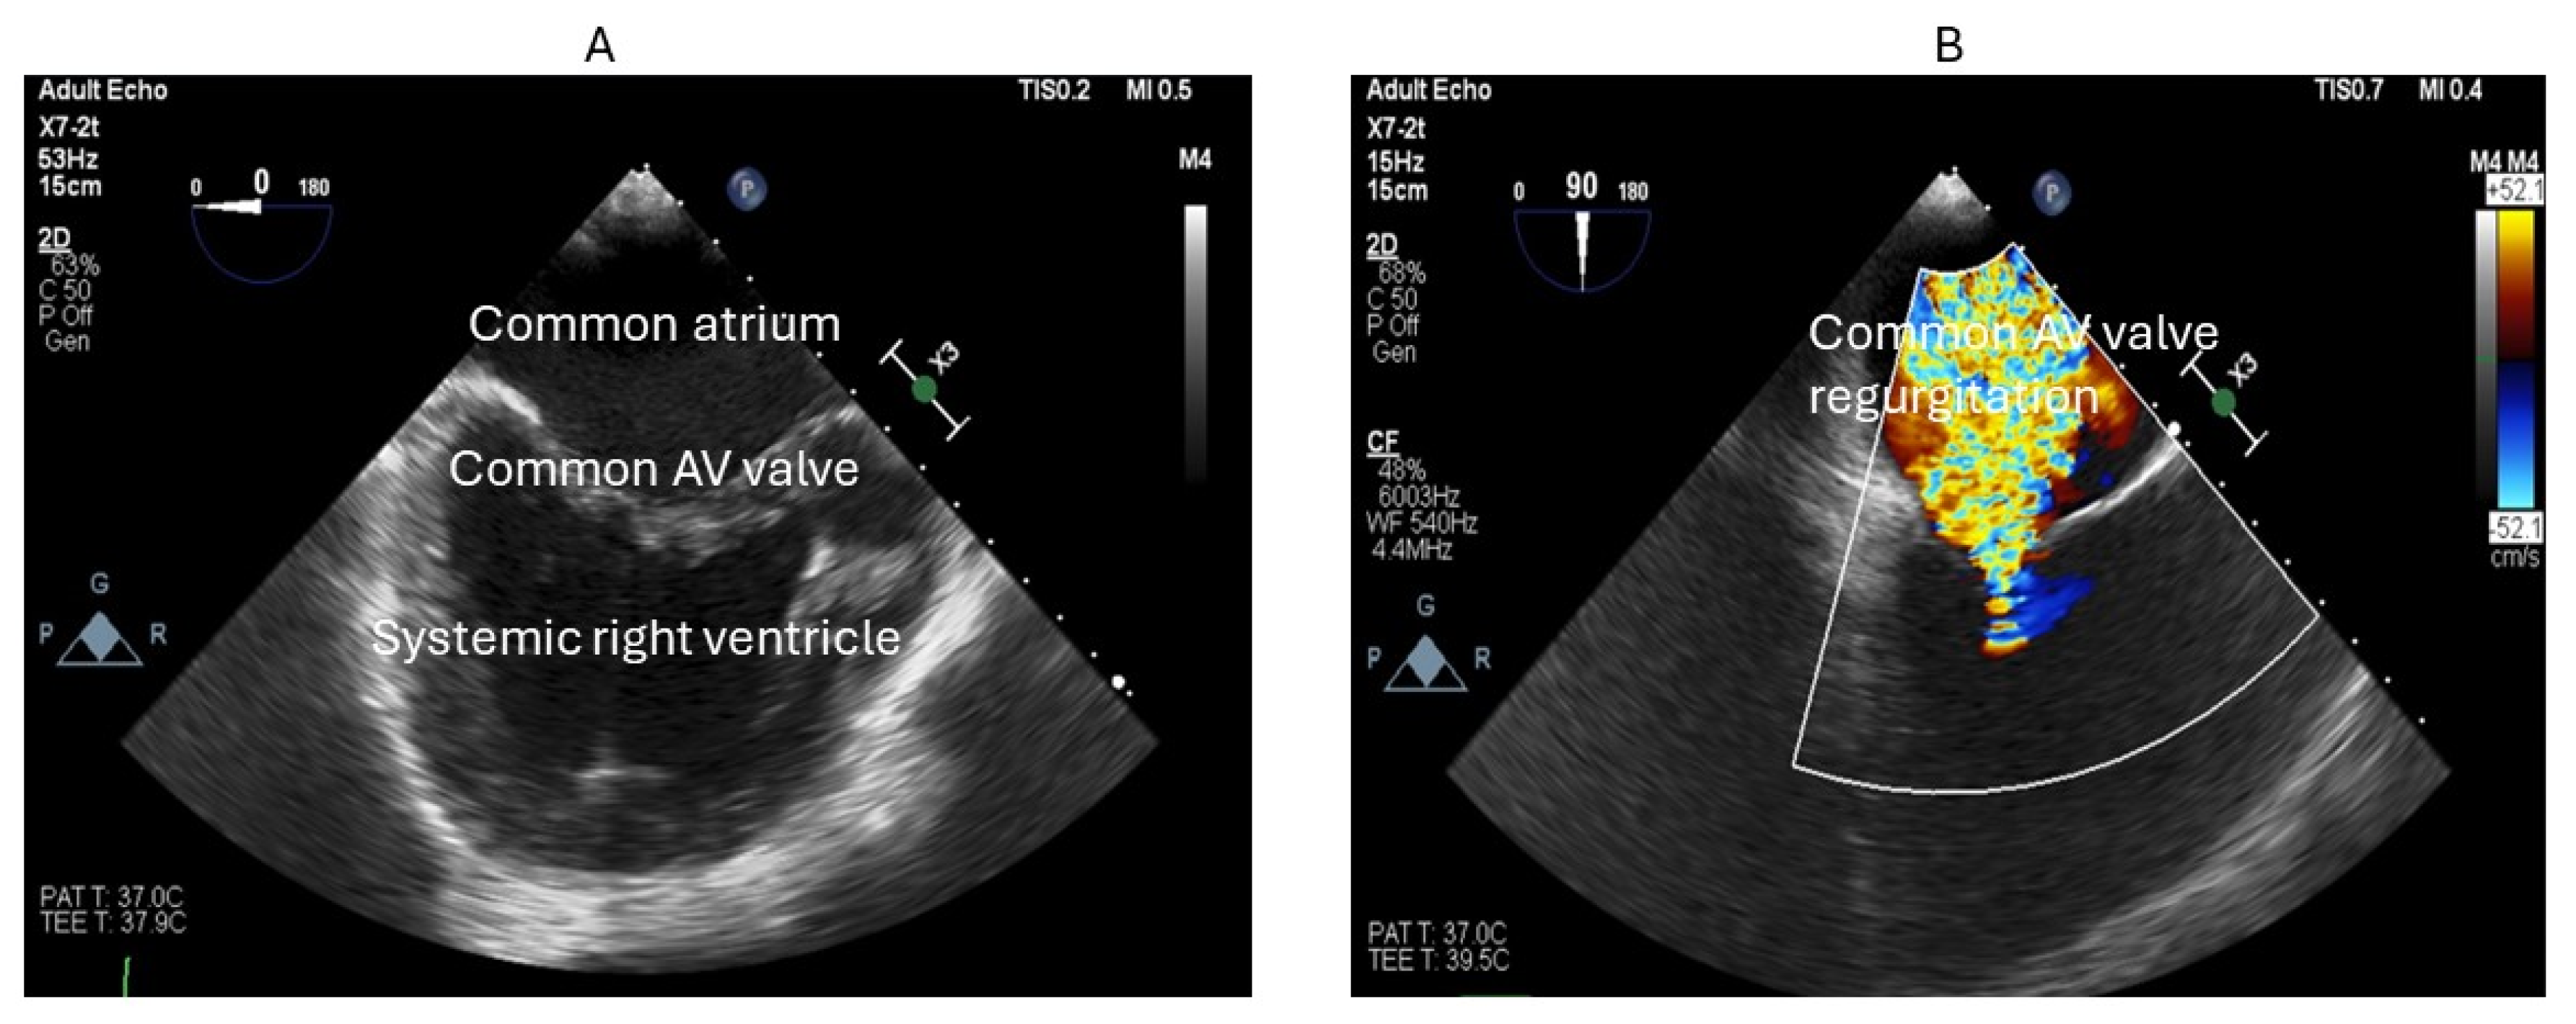

9. Atrioventricular Valve Regurgitation (AVVR)

10. Diagnosis of AVVR

26. Selective Lymphatic Duct Embolization plus Covered Stent Placement

29. Percutaneous Intervention for AV Valve Regurgitation